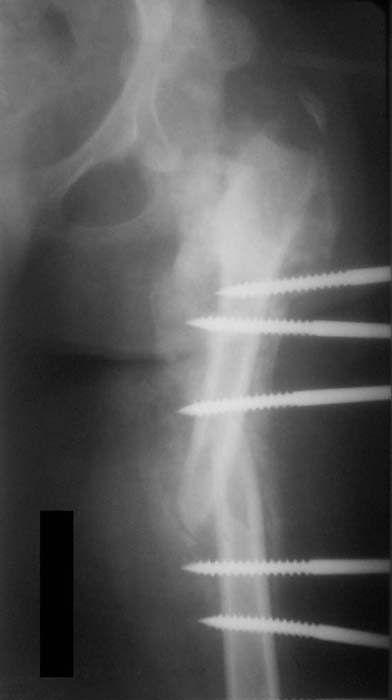

Пациентка 17 лет. В 5-летнем возрасте получила кататравму - осложнённый перелом позвоночника с повреждением спинного мозга в грудном отделе, нижняя параплегия с нарушением функции тазовых органов. Поступила к нам в отделение в сентябре 2007 по поводу патологического перелома левого бедра на фоне хронического остеомиелита бедра. Лечение стержневым аппаратом АВФ, достигнута консолидация. За время лечения развились массивные пролежни крестца и правого бедра с переходом в остеомиелит в/3 правого бедра, сепсис. Выполнено вскрытие гнойника, некрэктомия. Рана велась открыто. В дальнейшем - повторные некрэктомии, дермотензия.

>Можно наложить простейший аппарат таз-бедро и подвесить больного

Такая мысль тоже приходила. Не решились, так как:1.Выраженный остеопороз костей таза и бедра, больная тучная - высок риск того, что стержни не выдержат. 2.Сейчас больная передвигается в инвалидном кресле - хоть какая-никакая, а динамизация. Если лишить её этой возможности - застойная пневмония со всеми вытекающими...